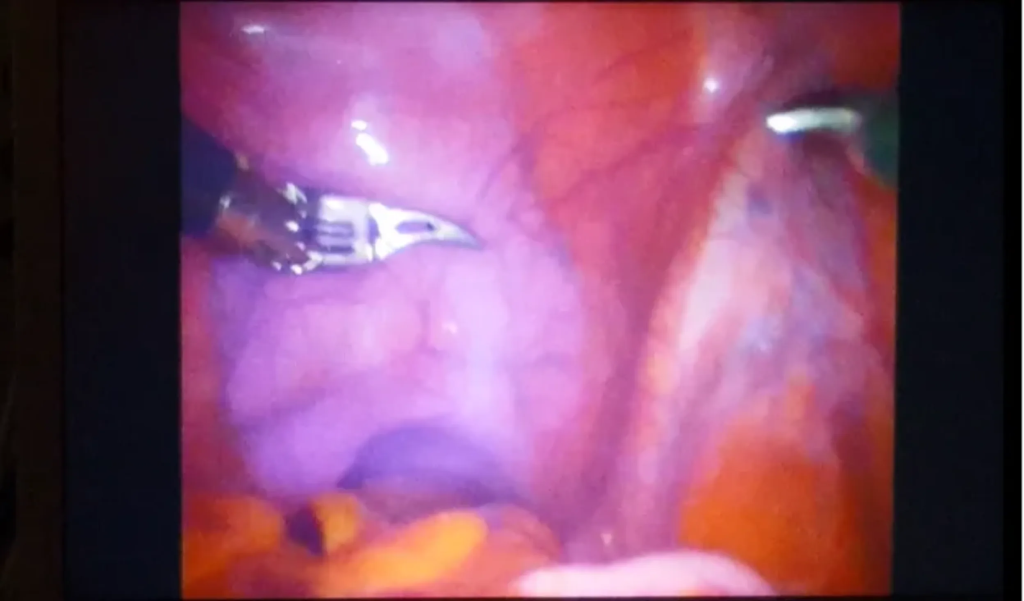

Surgeons begin a radical prostatectomy in the ProMOTE study, with prostate and lymph node tissue made visible by the purple dye.

In a preliminary study involving 23 men undergoing prostatectomies, the dye successfully attached to proteins on cancer cells, highlighting them for the surgical team with the help of a specially designed imaging system. Cutting out cancerous cells is crucial to curing the disease in early stages, but it can be extremely difficult to catch those that have spread outside the main tumors to lymph nodes and other areas of the pelvis.

The dye, which is linked to a molecule that targets Prostate-Specific Membrane Antigens, or PSMA, was developed at the University of Oxford in collaboration with a Southern California-based biotech company. A larger trial is currently underway in the U.K., and researchers are hopeful the dye could one day be used for other types of cancers as well.